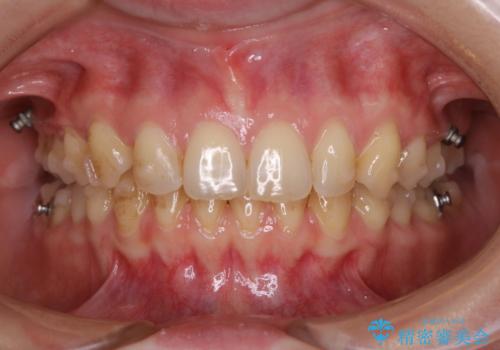

- 治療計画

- 定期的にメンテナンスで来院されている方から歯を白くしたいと相談され、自然な色味希望と歯の表面のべたつき感じからエアーフローとホワイトニングをご提案しました

メンテナンスしながら歯を白くしていく